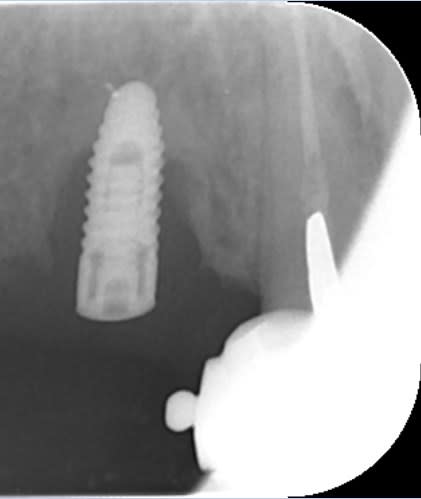

bon, suite...

je viens d'avoir les images...

autant sur la 11 çà paraît jouable...autant sur la 12 je pense que c'est mort!!!

faux canal, il ne reste quasi plus rien de la partie vestibulaire de la dent...

point positif: il semblerait que j'ai encore de quoi ancrer une vis sous les fosses nasales en apical de cette 12...

donc amha çà sent l'EII avec mise en vitrine immédiate...et si c'est le cas, je ne ferai pas de quartier à la 11...elle passera elle aussi à la trappe vu le risque de récidive et/ou de contamination du biomat qu'il me faudra mettre pour éviter que tout ne s'effondre...